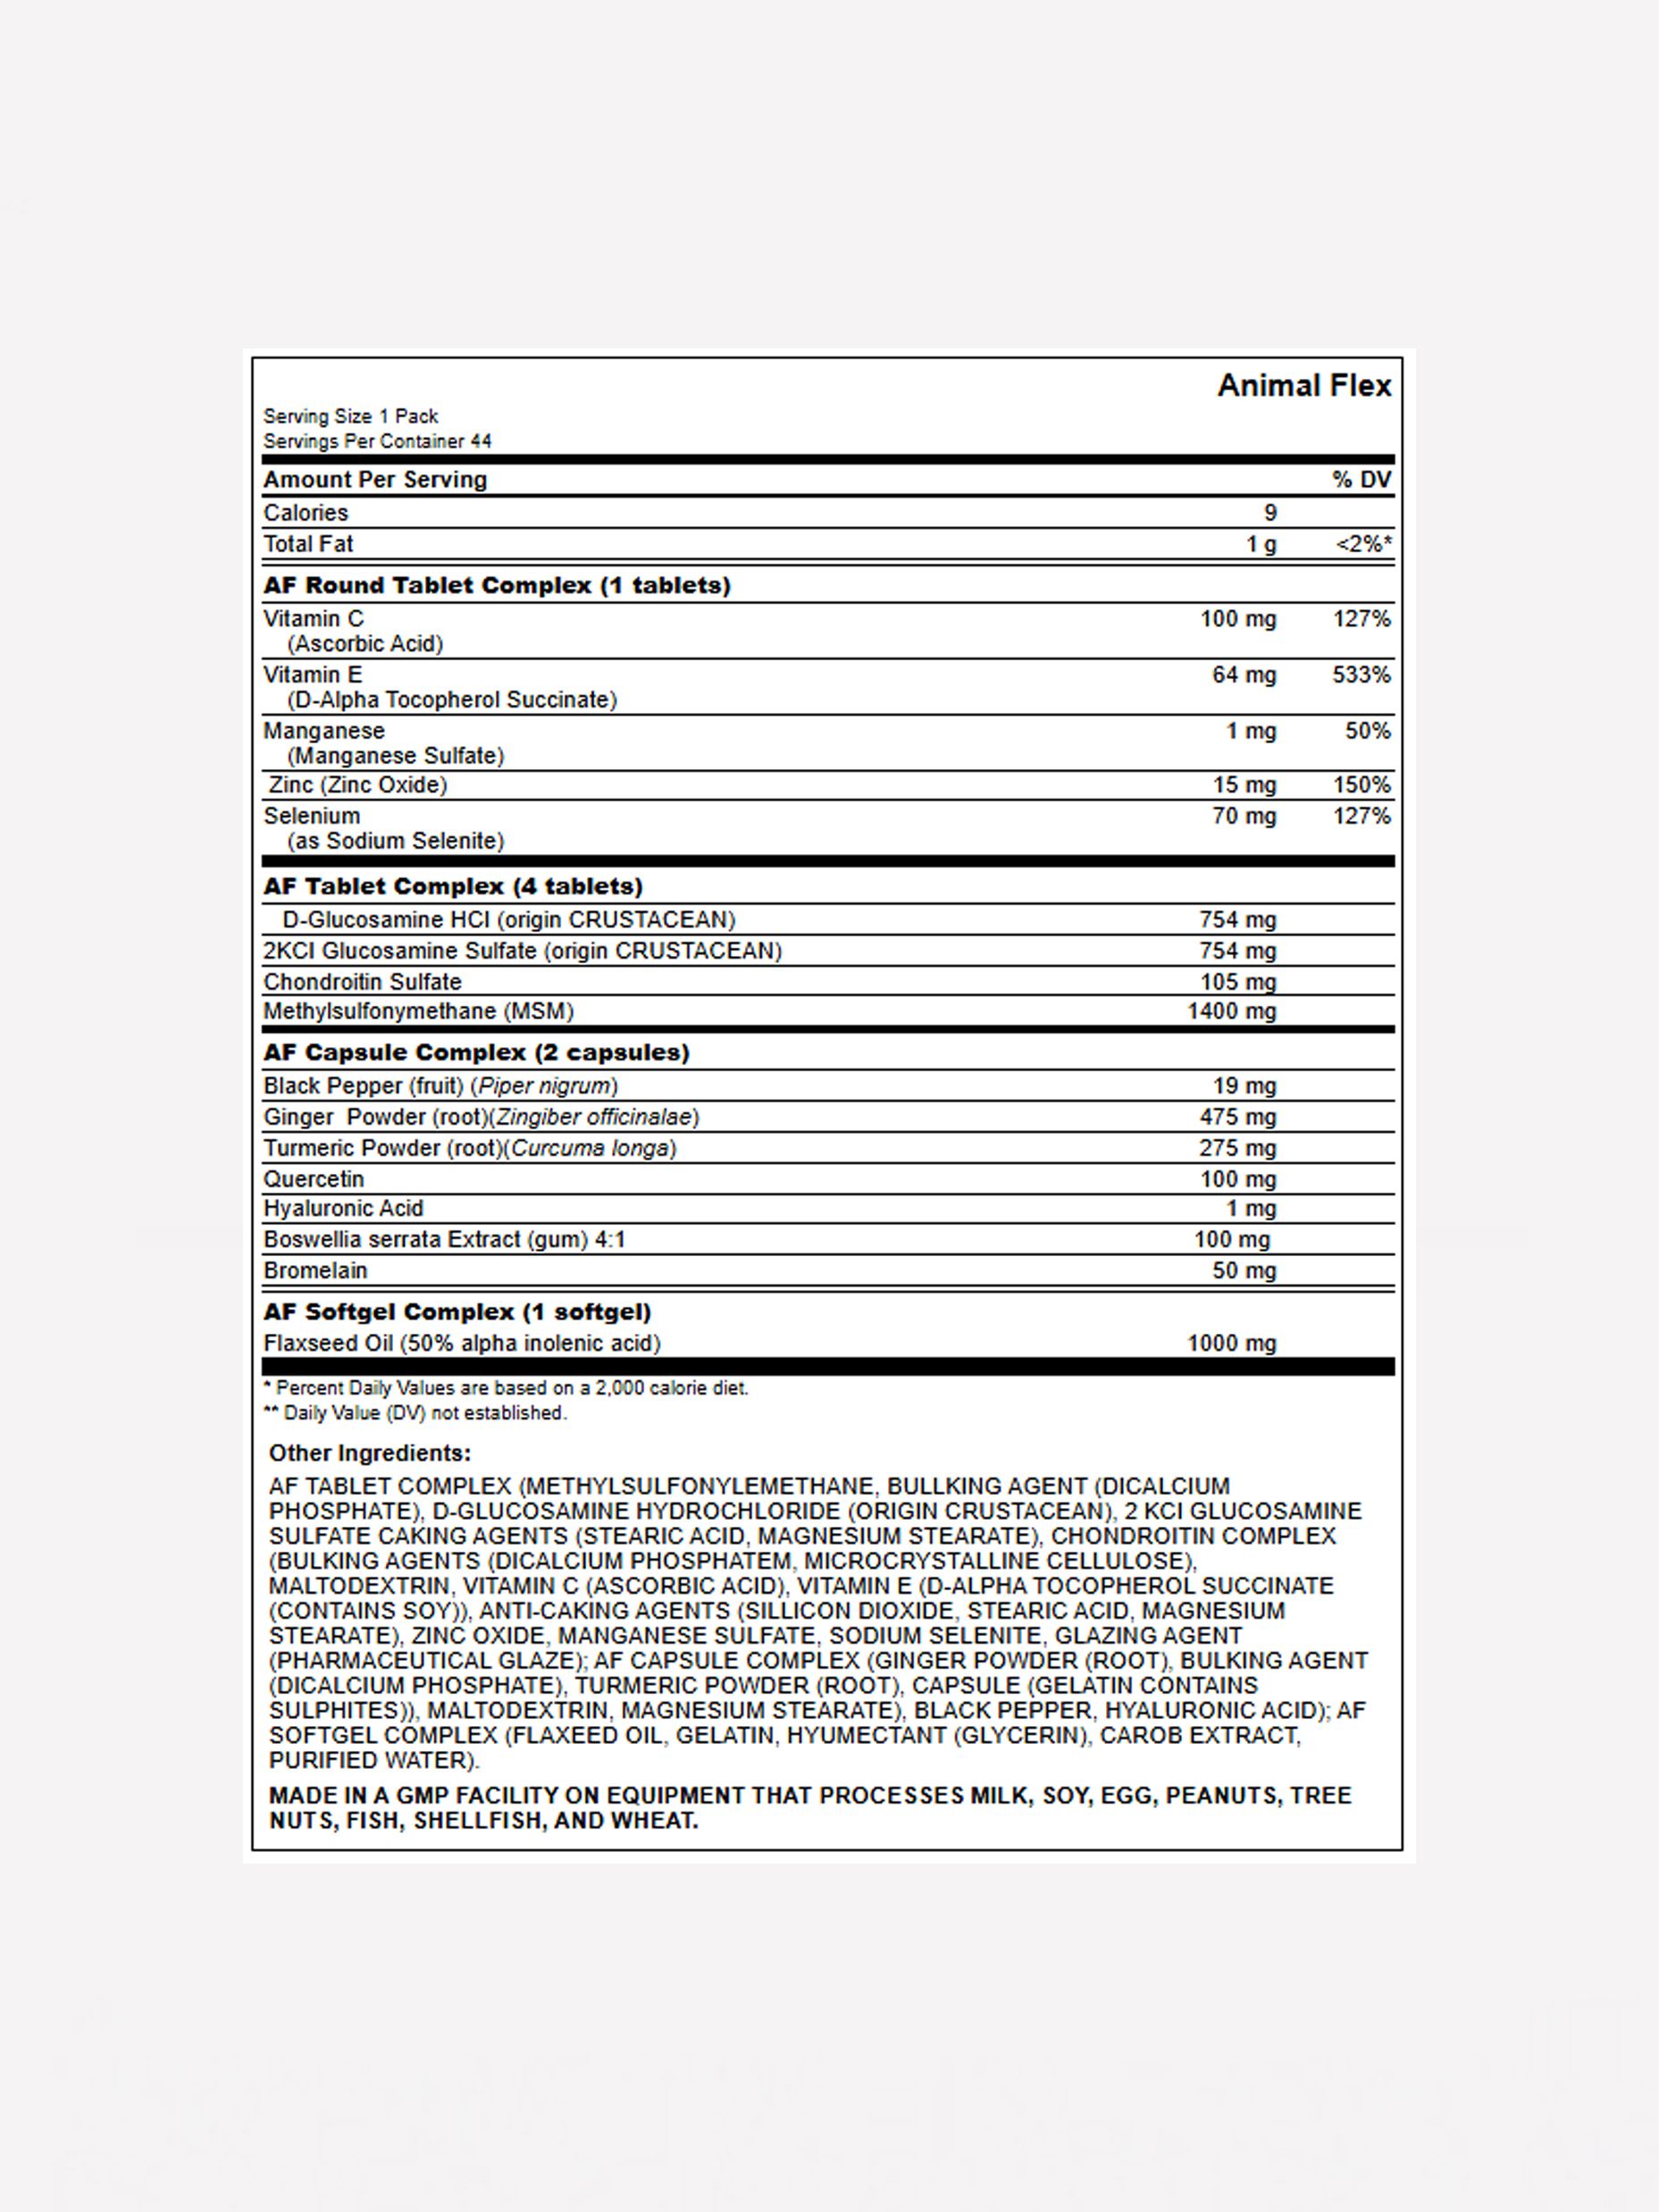

3어떤 성분들이 들어있나요?애니멀 플렉스들의 성분은 크게 세 파트로 나눠집니다. 관절 형성, 관절 윤활, 관절 서포트 파트로 나뉘어져 그 분야에 최고의 성분들이 모여있습니다.

4구체적으로 알려주세요먼저 관절형성 파트에는 관절 및 인대 형성에 중요한 글루코사민, 식이유황, 콘트로이틴 황산 A, C가 함유되어 있습니다. 관절 윤활 파트에는 알파 리놀렌산이 함유된 아마씨 오일, 세틸 미스톨레이트 블렌드. 히알루론산이 함유되어 있으며, 관절 서포트 파트에는 생강 뿌리 추출물, 강황 뿌리, 보스웨리아, 케르세틴, 브로멜린이 함유되어 있어 여러분의 관절 건강을 도와드립니다.

5다른 성분들도 있나요?이 세 파트 이외에도 아연과 비타민 C와 비타민 E, 셀레늄 등 다양한 성분들이 여러분의 신체를 지원합니다.

3어떤 성분들이 들어있나요?애니멀 플렉스들의 성분은 크게 세 파트로 나눠집니다. 관절 형성, 관절 윤활, 관절 서포트 파트로 나뉘어져 그 분야에 최고의 성분들이 모여있습니다.

4구체적으로 알려주세요먼저 관절형성 파트에는 관절 및 인대 형성에 중요한 글루코사민, 식이유황, 콘트로이틴 황산 A, C가 함유되어 있습니다. 관절 윤활 파트에는 알파 리놀렌산이 함유된 아마씨 오일, 세틸 미스톨레이트 블렌드. 히알루론산이 함유되어 있으며, 관절 서포트 파트에는 생강 뿌리 추출물, 강황 뿌리, 보스웨리아, 케르세틴, 브로멜린이 함유되어 있어 여러분의 관절 건강을 도와드립니다.

5다른 성분들도 있나요?이 세 파트 이외에도 아연과 비타민 C와 비타민 E, 셀레늄 등 다양한 성분들이 여러분의 신체를 지원합니다.